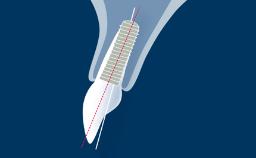

Após a extração dentária, um processo bem descrito de cicatrização ocorre no alvéolo. Uma série de eventos fisiológicos ocorre, resultando em cicatrização de feridas e regeneração óssea dentro do alvéolo. A reabsorção óssea resulta em alterações externas no rebordo alveolar.

O resultado dessa reabsorção é na maioria das vezes uma modificação significativa do contorno pré-extração da crista alveolar, que pode representar um problema para a reconstrução protética posterior. Por esse motivo, o conhecimento do processo de cicatrização após a extração dentária é essencial para o planejamento apropriado do tratamento com implantes sob orientação protética. Este módulo apresentará características anatômicas do osso alveolar e do alvéolo pós-extração e descreverá as alterações histológicas e dimensionais após a extração dentária.